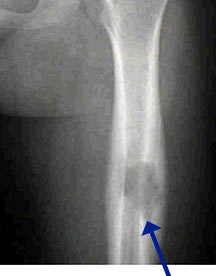

- May arise from any bone and any site within a bone (epiphyseal, metaphyseal, diaphyseal)

- Radiographically variable appearance: may appear benign (geographic) or malignant (permeative or moth eaten)